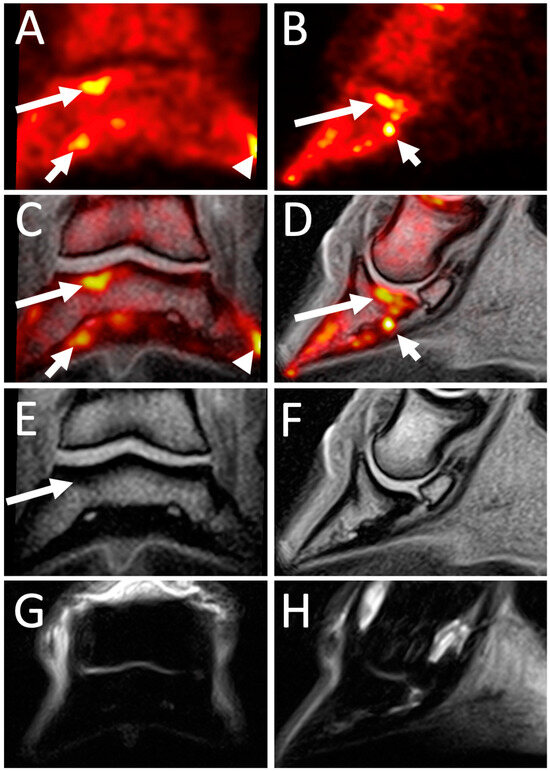

4.2. 18F-NaF PET Combined with CT or MRI for Optimal Bone Imaging

4.3. 18F-FDG PET Combined with CT or MRI for Staging of Soft Tissue Lesions

4.4. PET for Longitudinal Monitoring of Lesions